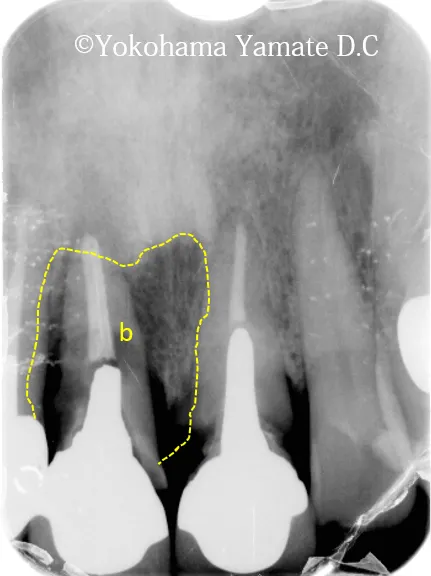

治療前(2020年11月初診時)

治療前骨欠損部・歯肉退縮部 b

上の顎の前歯のインプラント付近。bは骨の無いところ

歯肉の厚み0.12mm 骨の厚み1.92mmで凹んでいる